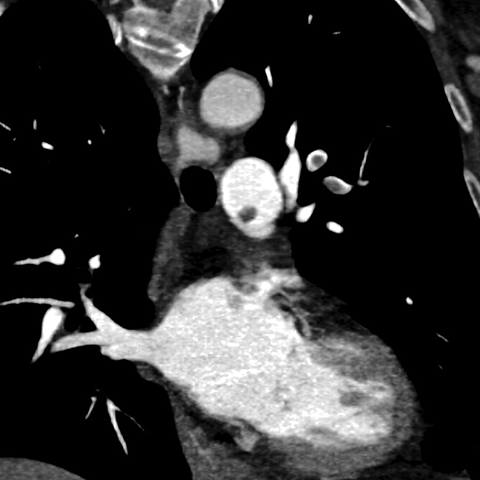

Acute Pulmonary Emboli (CT Pulmonary Angiogram) [2 of 3]